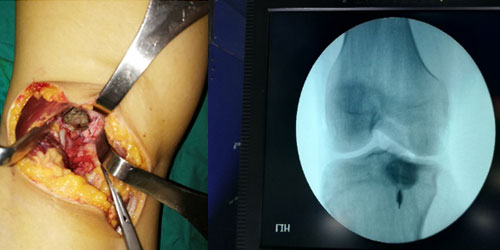

Спинальная метастаза представляет собой распространение рака на кости позвоночника, что часто вызывает боль в спине и другие симптомы. Ранняя диагностика и индивидуально подобранное лечение играют важную роль в улучшении качества жизни и эффективном контроле симптомов.